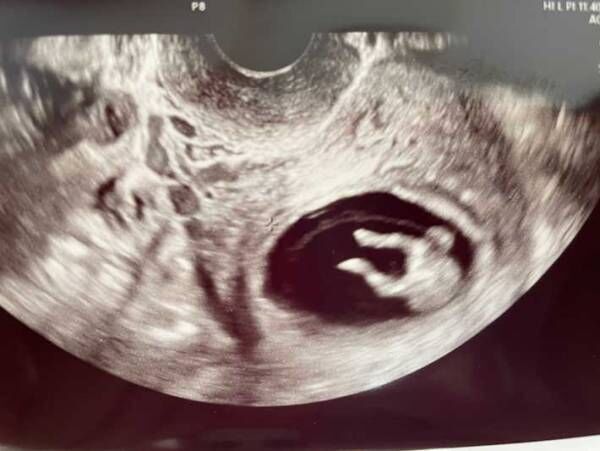

「足かわいすぎて、診察室の中、全員で笑った」

そんなコメントとともに、Twitterに公開された1枚の超音波写真をご紹介します。

人々が爆笑した理由が、ひと目で分かる、こちらの写真をご覧ください!

赤ちゃんの写真に、診察室にいた全員が爆笑! その理由がコチラです

ズコー!

なんと写真には、両足を宙へ放り出しているような、赤ちゃんの姿が写っていたのです!

まるでズッコケているかのように見える貴重な光景に、笑いがこみ上げます。